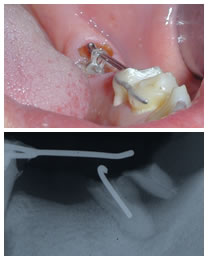

治療中

インプラント治療中エクストリュージョン中口腔内写真と同レントゲン